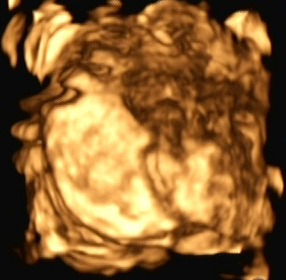

Ein zunächst durchgeführtes CTG war unauffällig. Im Rahmen der sonografischen Untersuchung zeigte sich der Fötus soweit beurteilbar zeitgerecht entwickelt. Dennoch konnte ein Anhydramnion festgestellt werden(Abb. 1, 2), weshalb auch kein fetales Gesicht darstellbar war (Abb. 3).